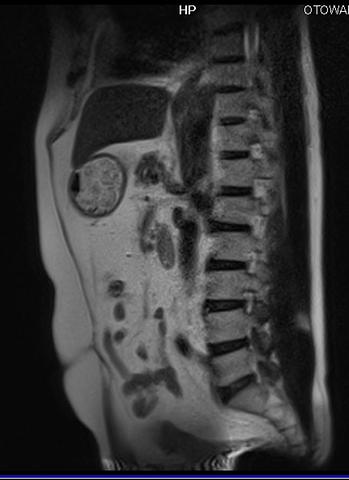

腰椎椎間板ヘルニア

ふくらはぎ痛いとおもったらMRI検査で腰椎椎間板ヘルニアと判明